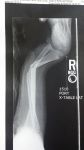

So, I was just minding my own business, not bothering anyone, when this boulder climbing wall comes along and.....you know..... starts making me climb it. Yada Yada Yada, two plates and 11 screws later, I am laying back in the recliner being thankful it was not worse!

Thanks All, Yes that is the before shot. I have not seen it since the surgery, so I am looking forward to that! Just trying not to overdo the Oxycontin and checking back here for inspiration. Tom

I can't look at your foot and ankle for long ... it makes me queasy ... it looks soooo damn painful ... unh ...